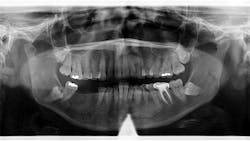

Patient: 40-year-old female

- Recurrent anterior mandibular swelling

- Two prior surgeries over the past six years to correct the condition

- Lesion previously removed when it was small and asymptomatic

- Patient pursued herbal treatment after second surgery